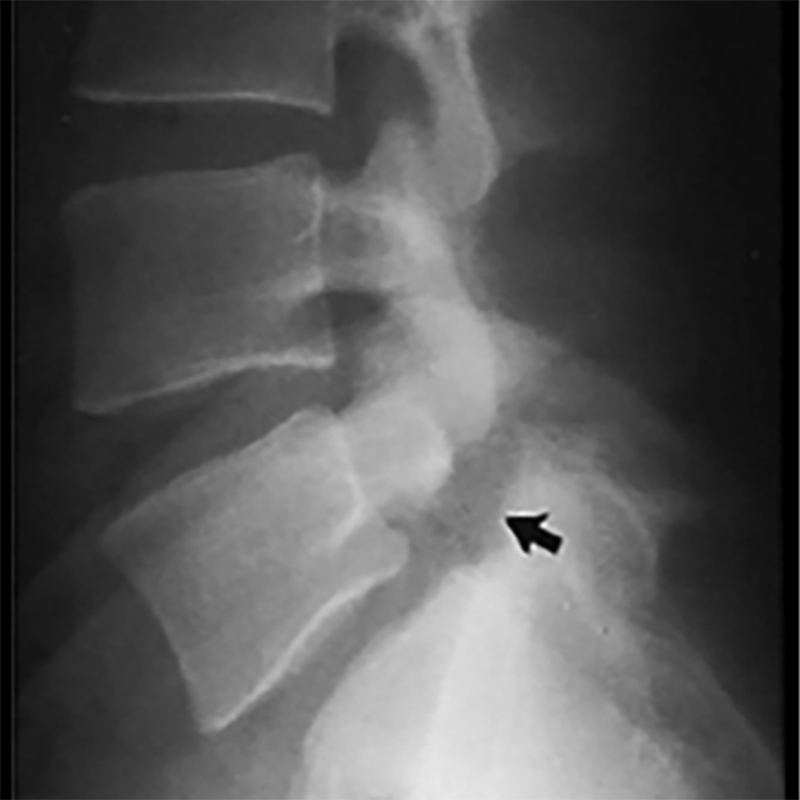

Mục tiêu Việc sử dụng vancomycin bột trong phẫu thuật cột sống để phòng nhiễm khuẩn vết mổ đã được thảo luận nhiều trong y văn. Nhiều nghiên cứu cho thấy sử dụng vancomycin bột tại chổ có hiệu quả giảm tỷ lệ nhiễm trùng sau mổ nhưng một số nghiên cứu khác lại cho thấy việc này không có hiệu quả. Hiệu quả của vancomycin trong giảm tỷ lệ […]